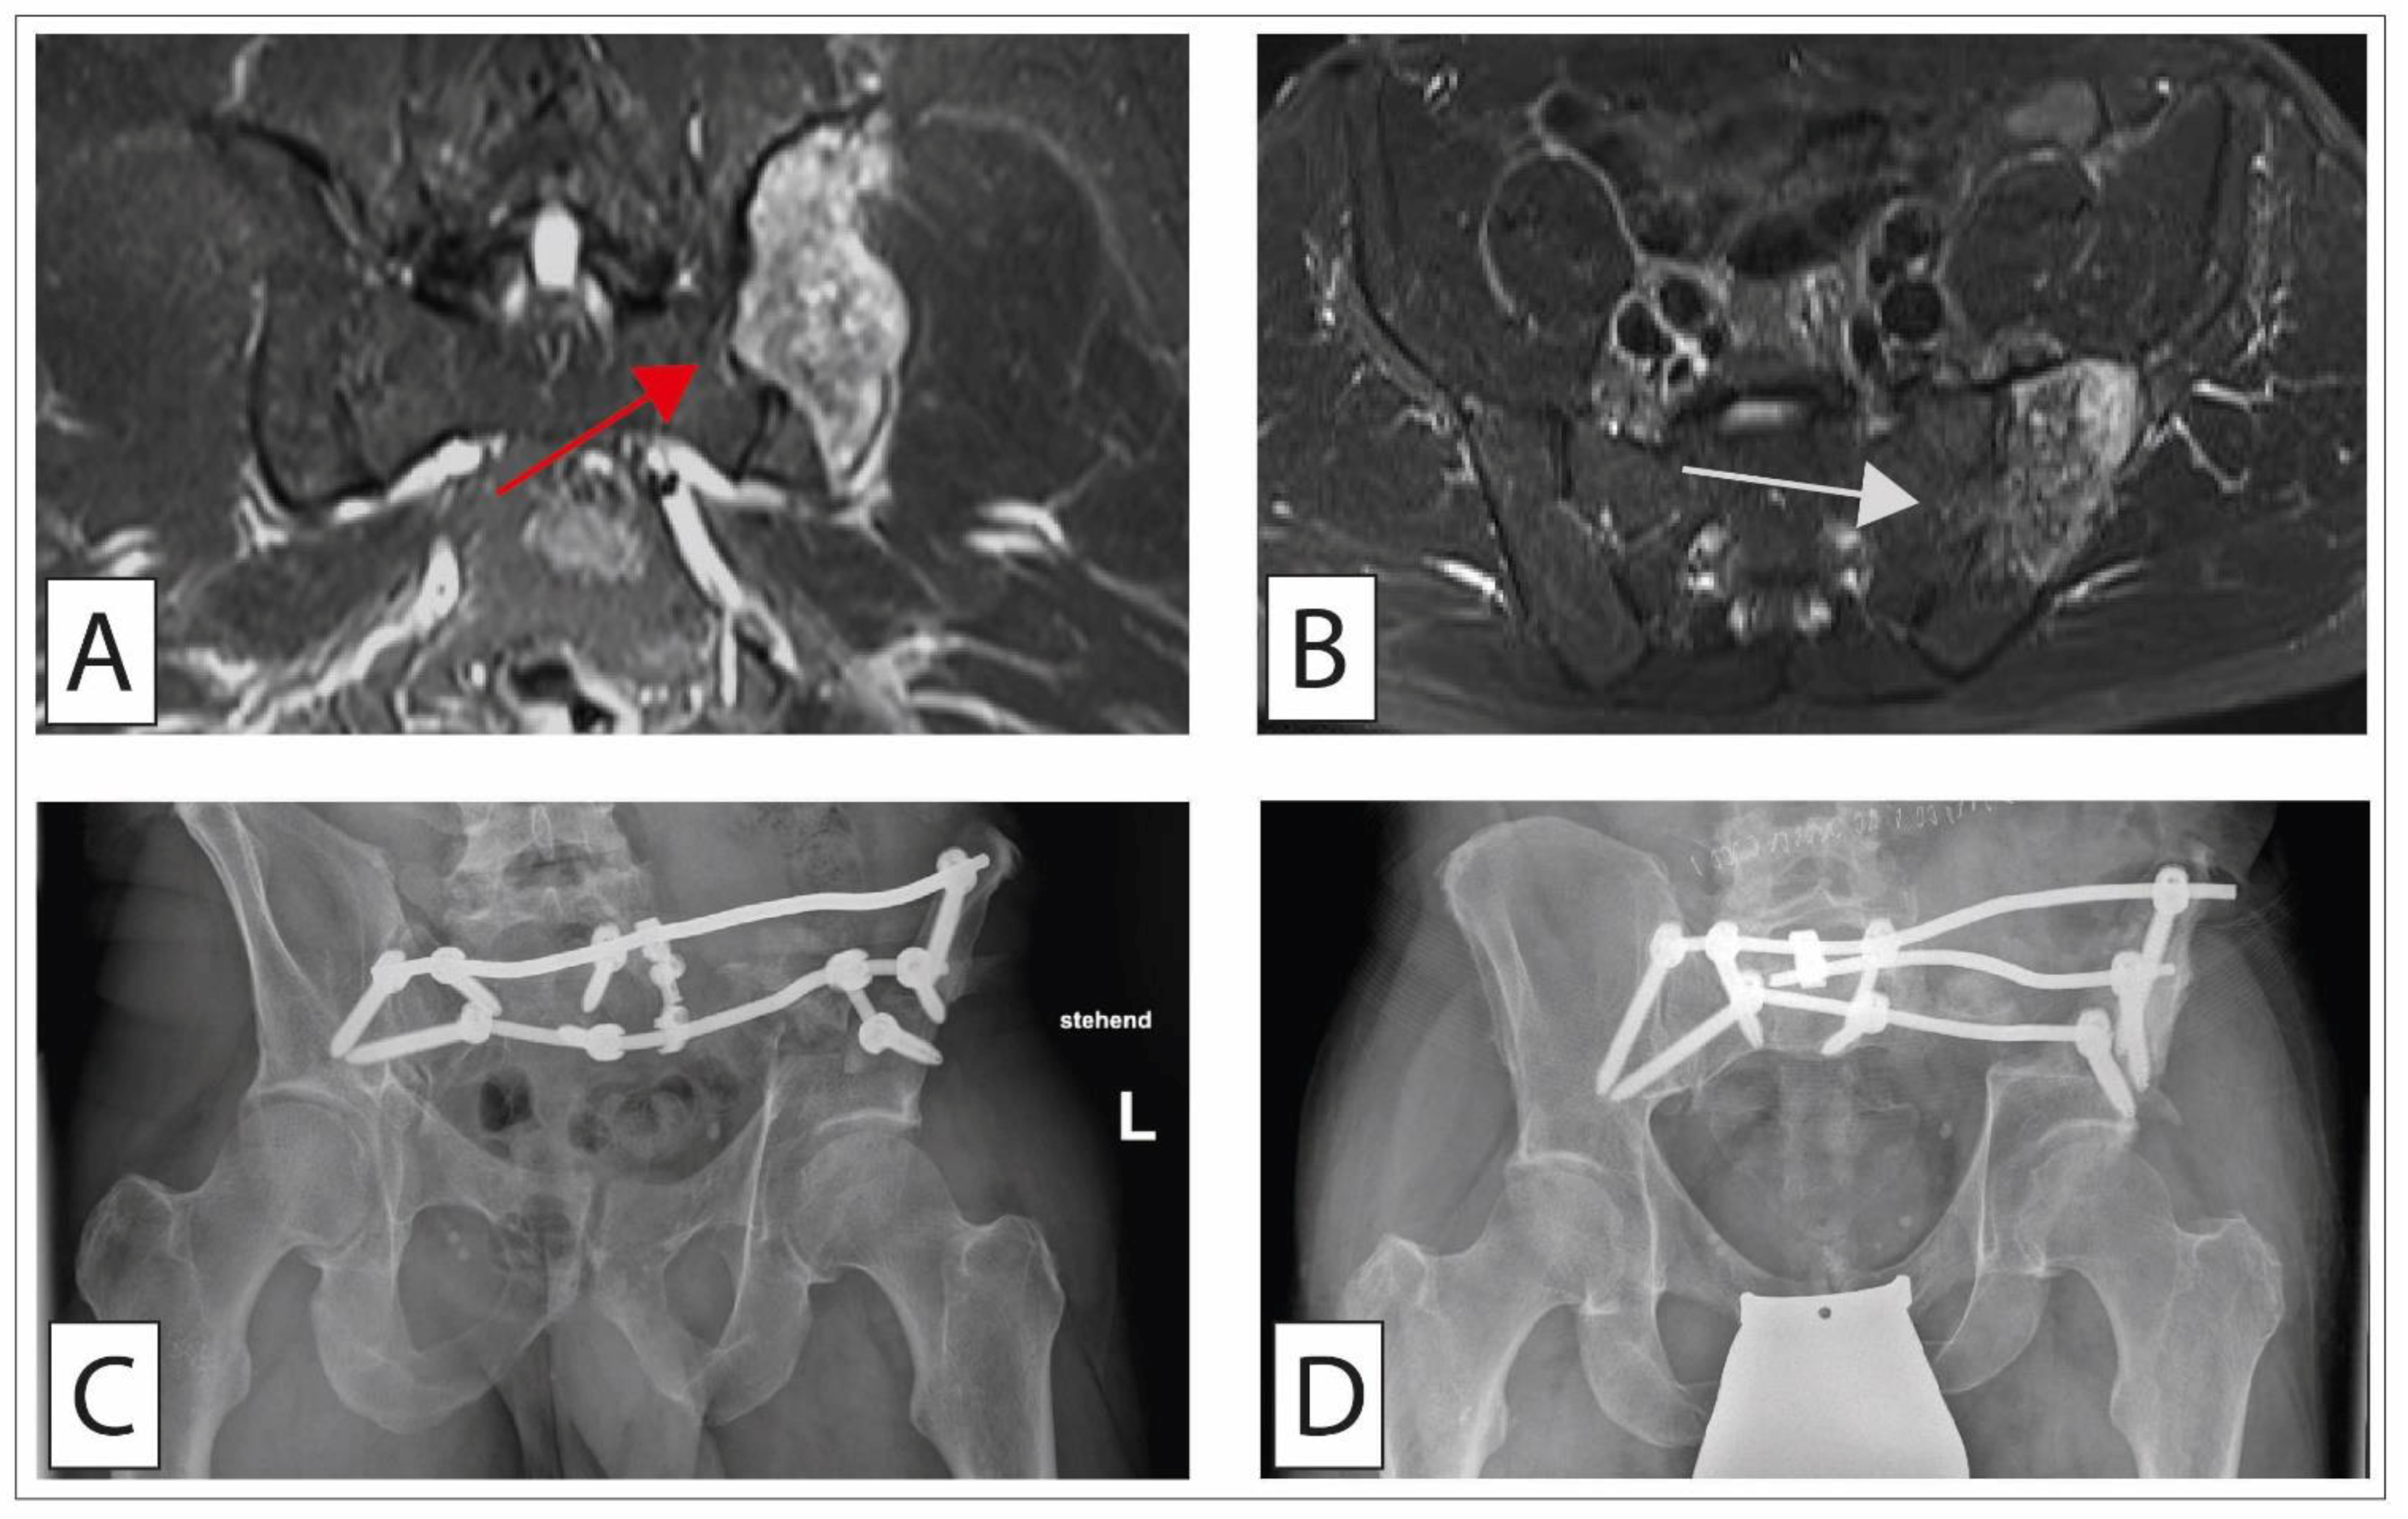

Pelvic Ring Reconstruction Using Double-Barreled Free Vascularized Fibula Graft (FVFG)

Reconstruction of the pelvic ring after resection of bone tumors is challenging. Erol et al. reviewed 16 children with pelvic Ewing sarcoma who had undergone pelvic ring reconstruction using double-barreled free vascularized fibula graft after sacroiliac resection. The fibula graft was placed between the supraacetabular region distally and the remaining ilium or sacrum proximally. The stability of the remaining pelvis and spinal column was secured by spinopelvic instrumentation. At the time of the final follow-up (mean, 49.8 months), 14 patients were alive while 2 patients had succumbed to the disease. The median Musculoskeletal Tumor Society score at that final follow-up was 80. The mean time for bone union was 9 months. Graft hypertrophy was found in all patients at 12 months. Seven patients had complications, three of whom required surgical revision due to one deep infection, one hematoma, and one wound dehiscence [73].

4.2.3. Surgical Treatment of Chondrosarcoma of the Pelvis

A unique situation is the presence of a central chondrosarcoma of the pelvic region (Figure 5). Chondrosarcomas of the pelvic region have an increased risk of metastasis and local recurrence (50% each). In addition, high demands are imposed on the surgeon for the surgical treatment since surgical procedures and reconstruction of the pelvic ring are highly complex [102]. A wide excision (>4 mm) should be the goal of surgical therapy, as smaller margins have an increased risk of early local relapse and of a reduced long-term survival [103]. At the same time, achieving these margins may entail the resection of nerves or nerve roots, which can be especially demanding for the patient in the case of the pudendal nerve. Subsequent reconstruction of the pelvic ring is challenging. Currently, reconstructions are performed by biological (e.g., hip transposition, massive allografts, autografts) or endoprosthetic reconstructions (e.g., allograft/prosthesis composites or prosthetic reconstructions). However, both allografts and autografts have a relevant risk of infection and/or fracture and often a postoperative leg length discrepancy is frequently observed [104]. Specially developed modular tumor prostheses demonstrated a reasonable functional outcome with long durability, with, however, also high infection rates [105]. Nevertheless, technical advances in design, structure, and fabrication have made such treatment strategies available for those patients affected by osteosarcoma of the pelvis.